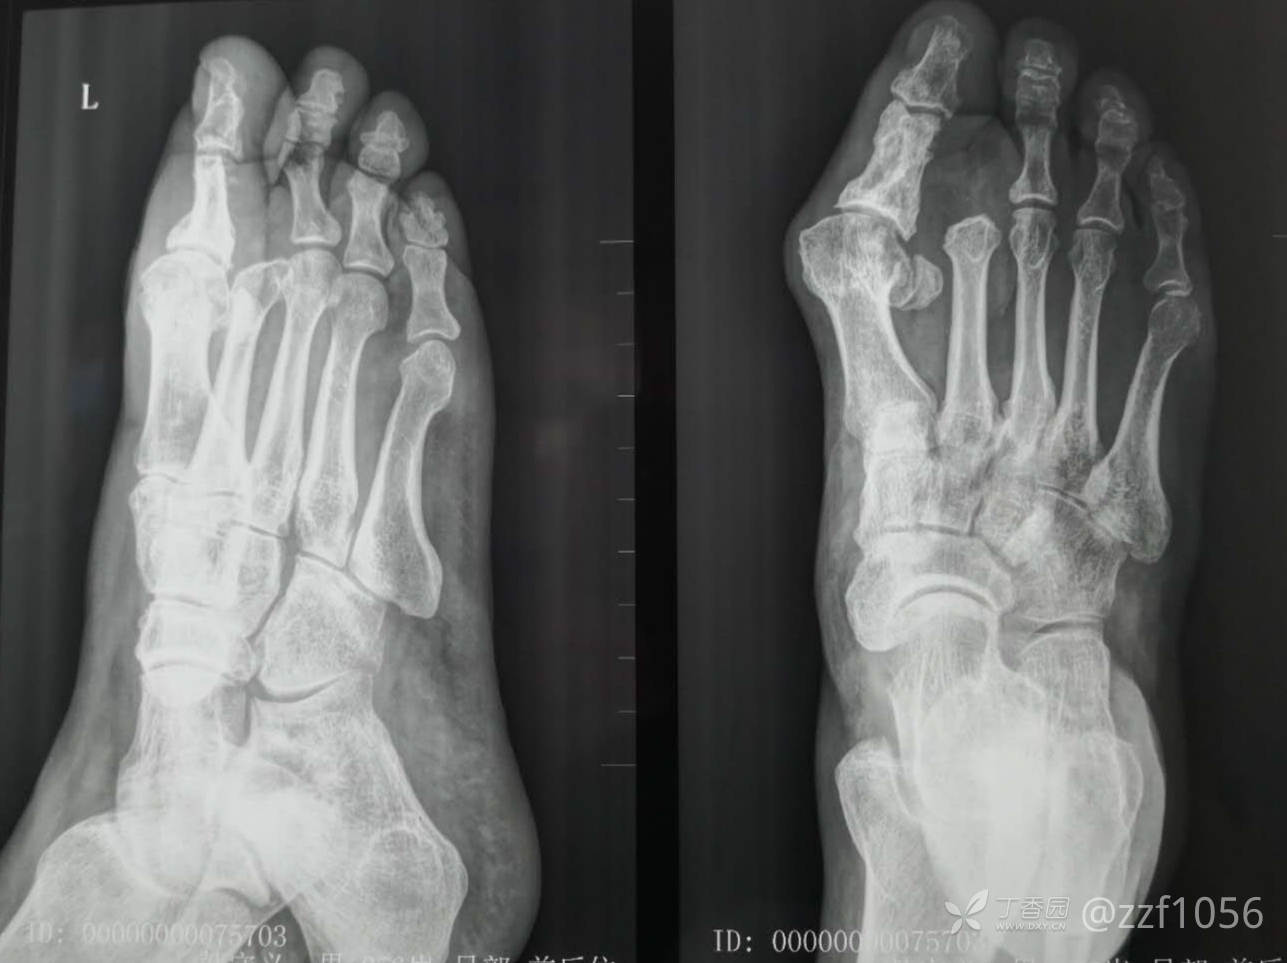

患者♂,54岁,左足压砸毁损骨外露,拇趾骨折,入院后值班医生清创固定,术后一周再次清创vsd,病房拆除vsd后设计游离腓肠内侧动脉穿支皮瓣修复。

该患者拒绝再次修整,对治疗满意,负重行走良好,不足-医源性拇外翻。